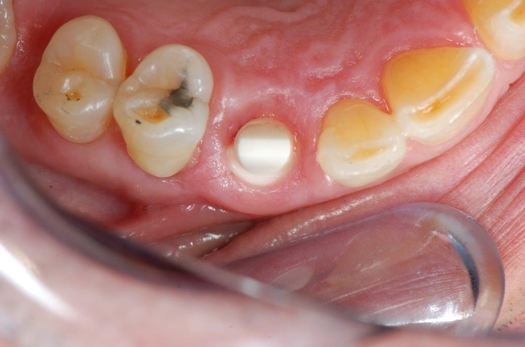

Fig 1. Preoperative surgery.

Figure 1

Figure 1 and Figure 2 depict the preoperative image and subsequent removal of three posterior teeth, immediate placement of zirconia-oxide ceramic dental implants, and soft-tissue augmentation with platelet-rich fibrin (PRF) to enhance the soft-tissue architecture surrounding the ceramic implants. The teeth were removed atraumatically and without suture placement. Because the implants were one-piece in stature (the abutment was incorporated into the implant), the recommendation was to splint the multiple units to minimize the lateral forces from mastication, swallowing, and tongue movement.